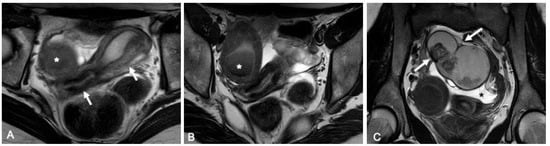

- O06. A Differentiated Approach to the Management of Patients with Ohvira Syndrome

Introduction: OHVIRA is obstruction of hemivagina and ipsilateral renal anomaly; among all malformations, 0.16–10% occur with a frequency of 1:2100 or 1:28,000 live-born girls. The etiological causes are unclear and practically unexplored; Diagnosis is usually delayed due to the presence of relatively regular menstrual function, leading to unjustified surgical interventions.

Aim of the Study: To analyze the clinical and anamnestic features of patients with OHVIRA.

Methods: 97 patients with OHVIRA aged 10–17 y who were treated at the pediatric and adolescent gynecology department from 2021–2023. Clinical and anamnestic data were studied.

Results: Urinary system defect was usually detected before hospitalization in 90.7%, ipsilateral renal aplasia in 78.4% (more often on the right), dysplasia/polycystic kidney 12.4%. From the moment of detection the anomaly of the urinary to a genital passed 6 y. The age of menarche 12 y. Periods continued for 6 days after 28–30, characterized by dysmenorrhea—75.3%. Irregularity of the cycle in 25.8%. Prior to hospitalization 57.7% had experience of previous examination and treatment, due to suspicion of acute surgical pathology 30.9%. 27.8% had a history of surgical treatment. Partial obstruction—the presence of fistulous communication between the hemivagina in 30.9%, unfortunately at the prehospital stage only in 2.1%. It should be noted that patients with partial obstruction were more likely to notice an earlier onset of dysmenorrhea, every second indicated the disappearance of pain after an episode of uterine bleeding, and 43.3% complained of prolonged pathological discharge.

Conclusions: The presence of abnormality of the urinary system in a girl, regardless of age, requires a mandatory examination by a gynecologist. The presence of early onset dysmenorrhea with a tendency to progression and/or prolonged pathological discharge, including recurrent episodes of uterine bleeding, is an indication for in-depth follow-up examination in order to exclude genital malformation.